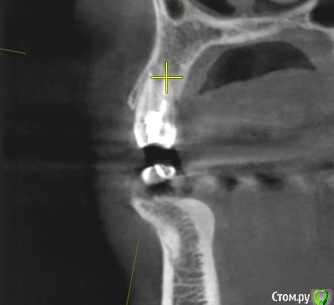

Tatiana72 Опубликовано 27 октября, 2020 Автор Поделиться Опубликовано 27 октября, 2020 Добрый вечер!Выкладываю скрины срезов Ссылка на исследованиеhttps://yadi.sk/d/ViQR0U6R2QjHzg Ссылка на комментарий

Дмитрий М Опубликовано 28 октября, 2020 Поделиться Опубликовано 28 октября, 2020 Добрый вечер!Выкладываю скрины срезовImage4.jpgImage5.jpgImage9.jpg Ссылка на исследованиеhttps://yadi.sk/d/ViQR0U6R2QjHzg не волнуйтесь всё хорошо, по КТ корень зуба не задетесть небольшой очаг разряжения на одном из апексов, обратитесь к стоматологу 1 Ссылка на комментарий